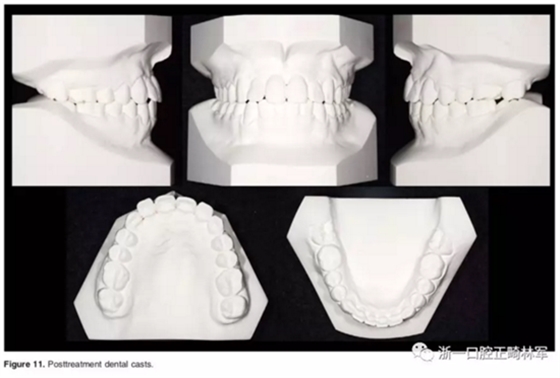

口外相:前牙易位、阻生均得以正確糾正,牙周組織健康。

口內(nèi)相及模型:I類尖牙、磨牙關(guān)系,覆合、覆蓋正常;中切牙與側(cè)切牙間有輕微的轉(zhuǎn)矩差;牙齦外形可;此外,在治療期間病人的口腔衛(wèi)生不夠良好,導(dǎo)致幾顆牙齒出現(xiàn)了齲病。